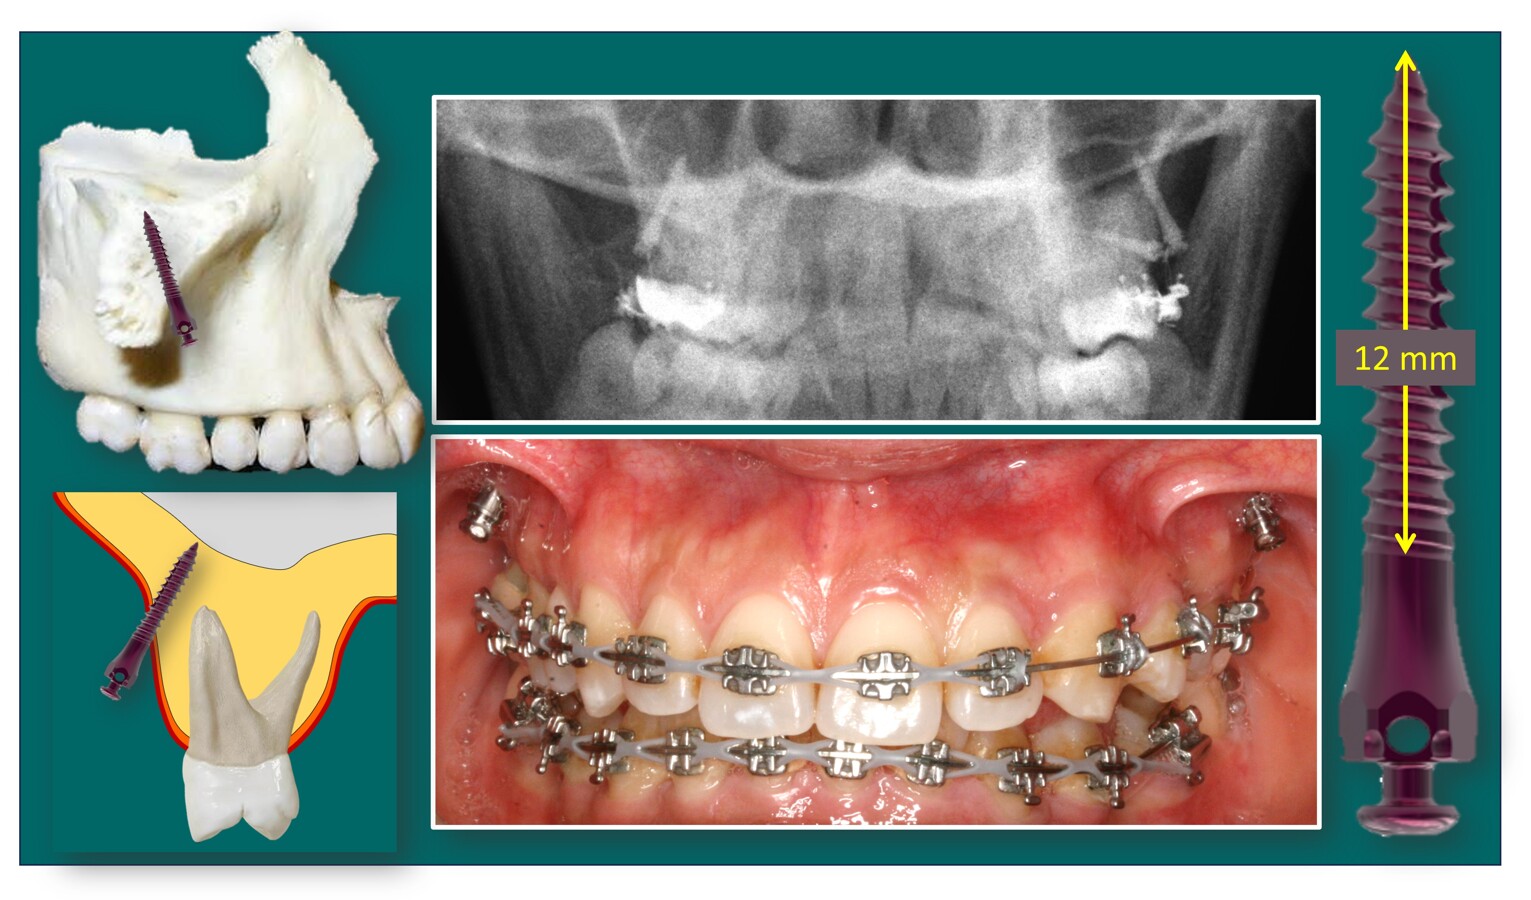

Con los microimplantes extraalveolares e infracigomáticos DSQ podemos favorecer la pasiva anterorrotación mandibular y el cierre de la mordida. Esquema de antes (izq.) y después de la intrusión dentoalveolar (der.).

Muestra del uso de microimplantes infracigomáticos DSQ para el control vertical maxilar.

Microimplantes infracigométicos DSQ para Ortopedia Dentofacial en el adolescente y el adulto.

Cambios faciales radicales sin necesidad de cirugía ortognática, solo con microimplantes intra y extraalveolares DSQ (Ziacom Medical Co.).